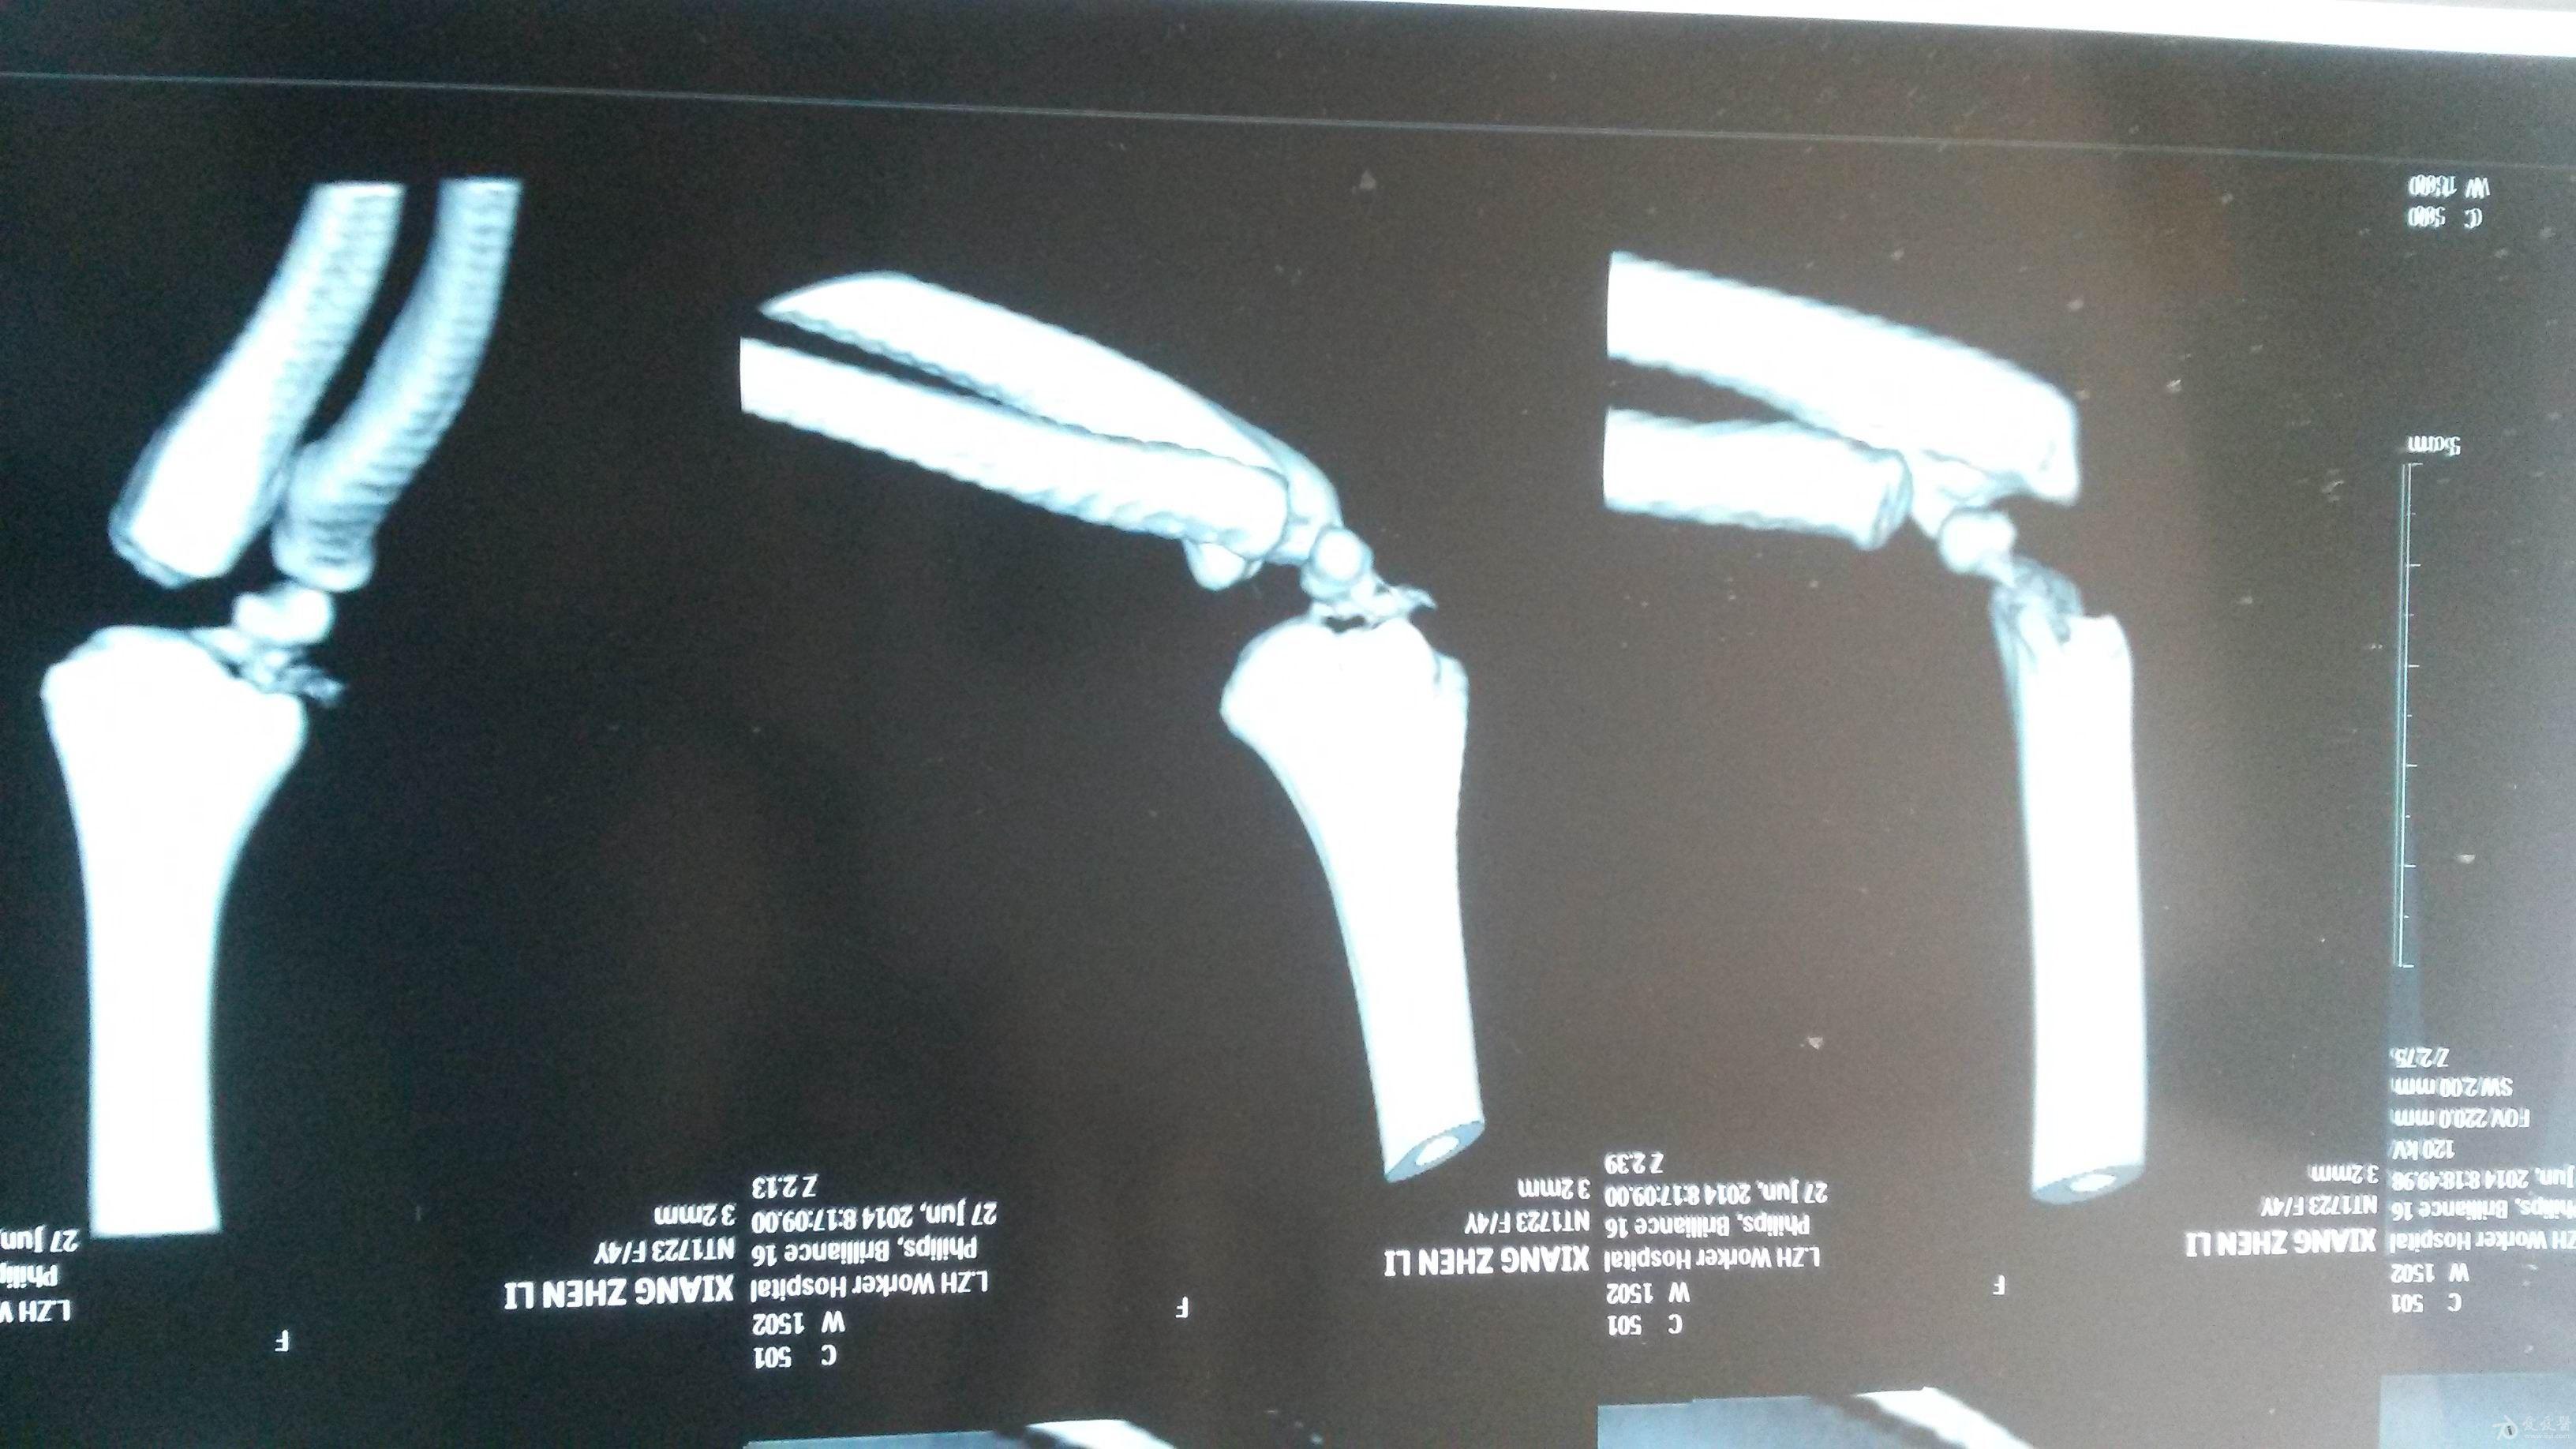

肱骨外髁骨折程度[s0]肱骨外髁骨折分型[s1]肱骨外髁骨折的临床表现[s2]肱骨外髁骨折Ⅲ型复位手法[s3]肱骨外髁骨折,保守治疗可以吗[s4]小儿肱骨外髁骨折[s5]儿童肱骨外髁骨折,医生不说你很可能永远都不会知道的[s6]不同类型的肱骨外髁骨折[s7]肱骨外髁骨折概述[s8]六、肱骨外髁骨折 - 图1[s9]六、肱骨外髁骨折 - 图2[s10]图片[s11]肱骨外髁骨折 m.haodf.com[s12]图片[s13]肱骨外髁骨折[s14]img[s15]肱骨外髁骨折.[s16]分期矫正儿童肱骨外髁骨折不愈合伴肘外翻畸形[s17]肱骨外髁骨折[s18]肱骨外髁骨折翻转90°,复位后克氏针或螺钉固定(自ao)[s19]右肱骨外髁骨折切开复位内固定术[s20]img[s21]img[s22]赵景新's media[s23]一例儿童右肱骨外髁骨折病例[s24]肱骨外髁骨折,保守治疗可以吗[s25]小儿肱骨外髁骨折[s26]肱骨外髁骨折固定[s27]肱骨外髁骨折 www.iiyi.com[s28]小儿肱骨外髁骨折的诊断和治疗[s29]右肱骨内外髁骨折[s30]图36-48 肱骨外髁骨折的不同程度移位 a型无移位;b型中度移位;c型完全移位伴旋转[s31]肱骨外髁骨折 www.haodf.com[s32]肱骨外髁骨折 www.haodf.com[s33]问:左肱骨外髁骨折,左肘关节脱位,6.[s34]儿童肱骨外髁骨折 - 小红书[s35]儿童肘关节损伤之--肱骨外髁骨折[s36]▲右侧肱骨外髁骨折闭合复位克氏针固定及石膏固定术后。“幸亏在掉落的[s37]肱骨外髁骨折 www.guahao.com[s38]肱骨头及外髁骨折,求诊治方案,手术还是非手术[s39]